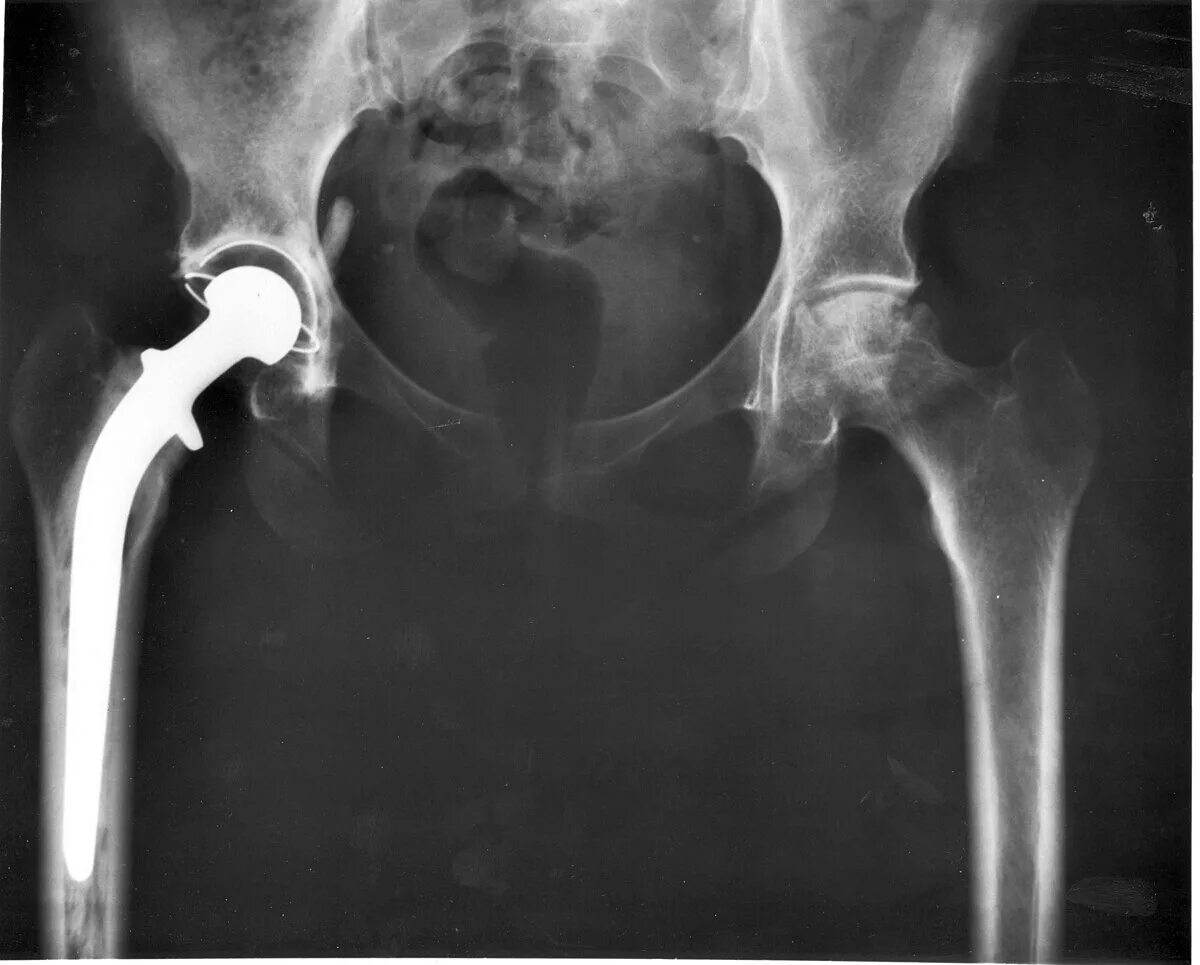

Этапы эндопротезирования тазобедренного сустава